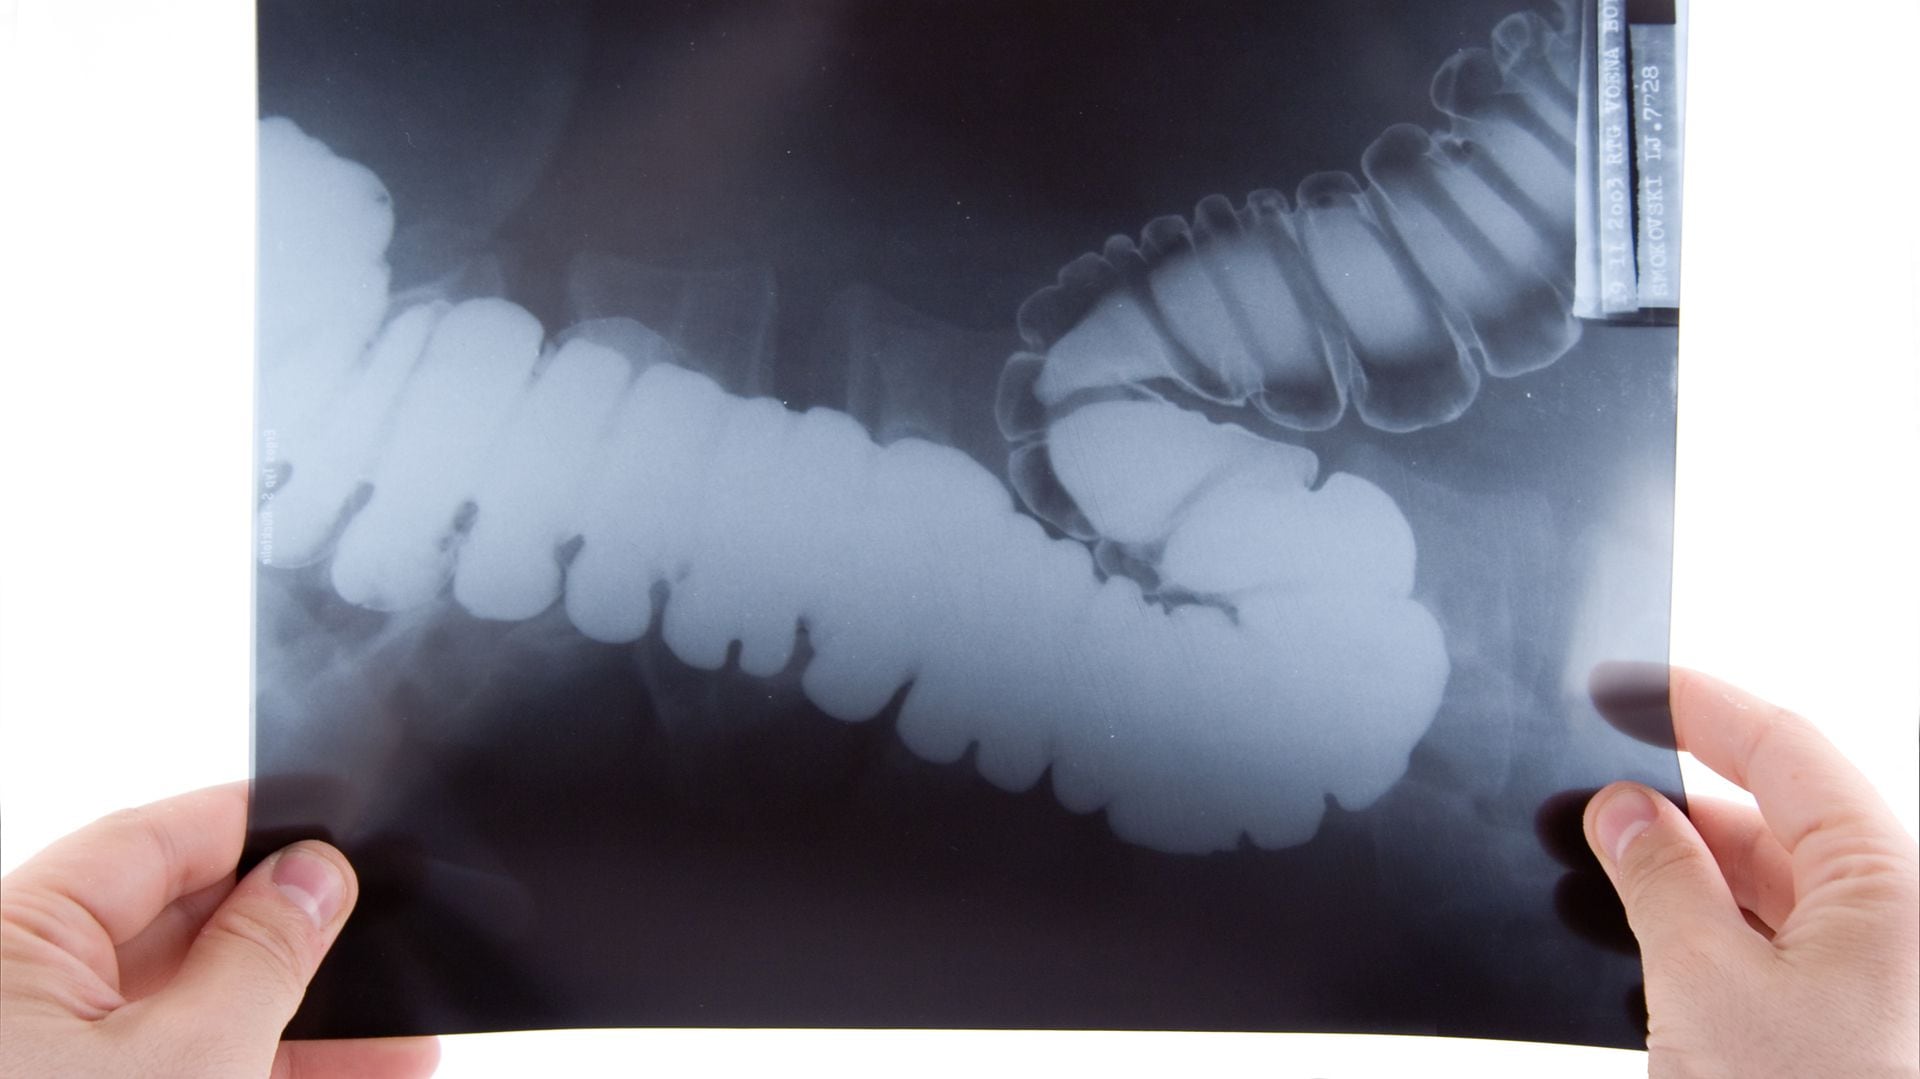

The fecal occult blood test and colonoscopy are the two most used studies to prevent or detect this type of cancer early. The first is performed by each patient at home with simple medical equipment and colonoscopy is performed in specialized centers with mild sedation under anesthesia, to examine the inside of the colon and rectum with a camera with a flexible tube. This is a routine examination, carried out by experienced professionals and with advanced equipment that allows the removal of a polyp at that very moment. Although colonoscopy may still generate reluctance among some patients, it is a painless and life-saving procedure.

These are two studies that differ in sensitivity, specificity and safety. They are used according to availability, accessibility and medical recommendation, analyzing each case in particular. If an occult blood test is positive, the next step is to perform a colonoscopy to identify the cause of the bleeding.